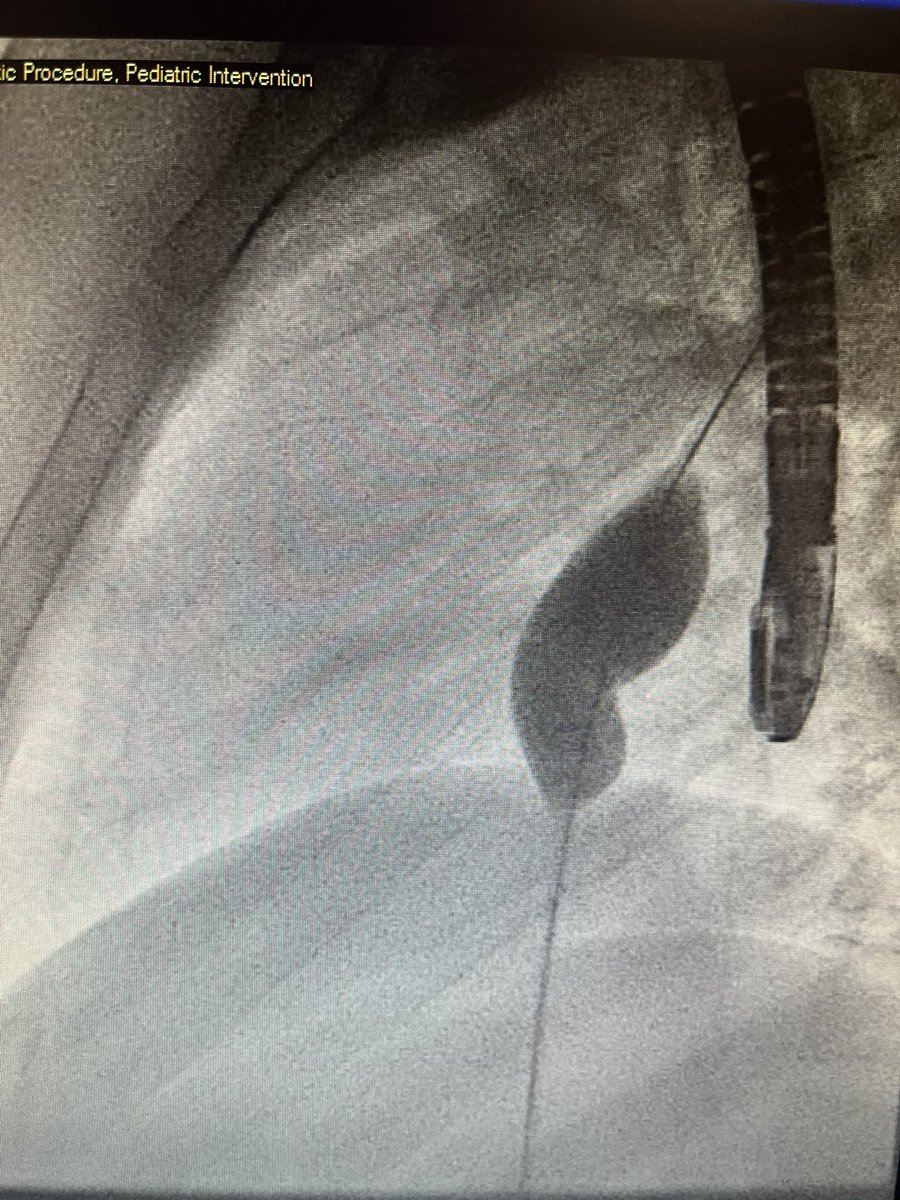

#Fontan patients offer unique challenges! Teenager with #HLHS post Fontan with recoarctation and LPA stenosis. LCA ran along the course of the LPA. Did coronary compression testing but able to stent both with good result. #CHD #ACHD @NCProvider @Adam_Skaff @SohamDasguptaMD 1/2